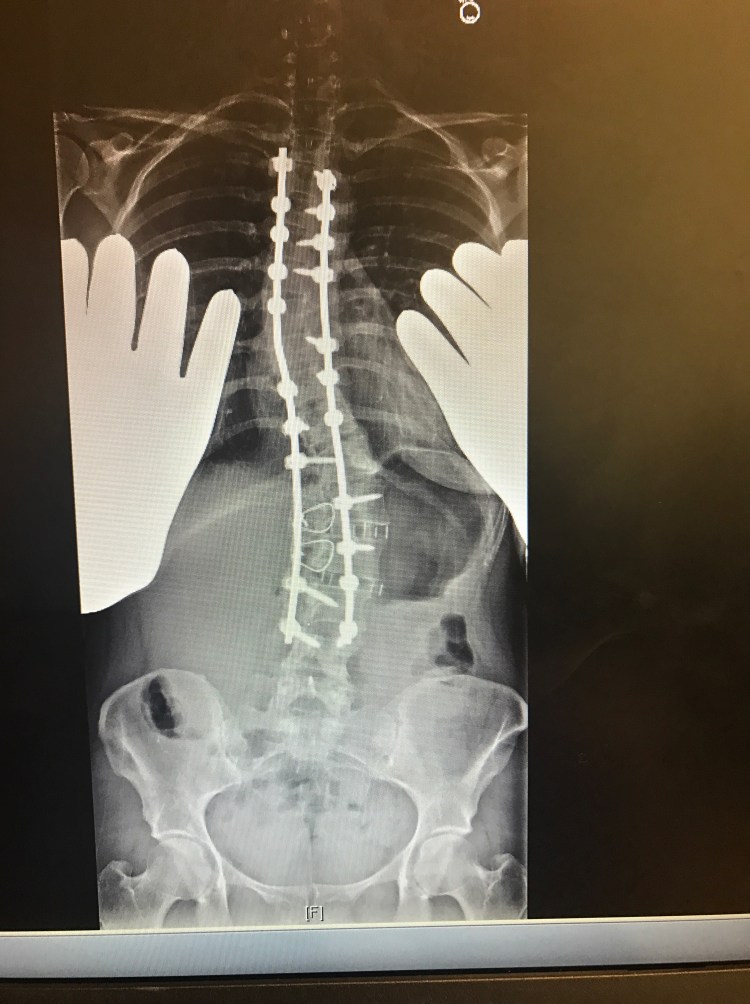

Last week, on Will’s birthday, it was also my 5 month post op appointment. I had a long list of questions and concerns and I was extremely anxious. These appointments always make me nervous and give me anxiety. While in the car on the long drive there, I can’t help but think about everything that happened and how it is going to affect me for the rest of my life. The feeling of these long rods screwed into my spine will never go away although hopefully get easier to forget about over time. I will never be able to bend my back or twist or bend side to side EVER. I still get asked this on a daily basis. The answer is never. Then, I have to continue to be cautious and not slip or fall or do anything that could cause a screw or rod to break and hope upon hope that these rods and screws can last the duration of my life without needing to be replaced. I already know somewhere in the future I will need another surgery to fuse the last few levels to my pelvis and boy am I already dreading for that day to come. Sorry to be a Debbie Downer. I guess it’s hard when people think because I am back at work, or can drive Will to preschool or wrap some damn Christmas presents that I must be “better”. Anyways…..my Doctor said that my bones are fusing. One side is fusing better than the other, but she is hopeful that the other side will catch up. She thinks that the first few months and all the added stress on my body prohibited me from really recovering until just recently. Fusions also can take up to 2 years from surgery to heal completely. All my screws are in place as well. We agreed I need to continue with physical therapy. Last week, I began light core muscle exercises with some resistance to help build my stomach muscles back up. Right now, I am having trouble standing up all the way do to the tightness in my hips and hamstrings. When I am not standing straight, it causes my back muscles to fire up causing some pretty crappy back pain. There’s still a long way to go to get this leg working and my shoulder is still causing me trouble as well. I am also still having blackout and dizzy spells which we had attributed to medicine, however, since being off everything for the most part, I am still having these multiple times a day. I was told I need to see a neurologist and get a primary doctor to run some tests.

You look great. Your xrays look even straighter now!!! Do you live in Cali? Im trying to figure that one out because your dressed like its cold and i thought you lived in Cali. Who was your surgeon again.? God Bless. Your a strong woman and sounds like you have a great supportive husband.

Yes in Northern California. Our weather can be in the 100’s in summer and in the 30’s in Winter. My back is actually a little less straight than right after with settling, but definitely staying put and starting to fuse!